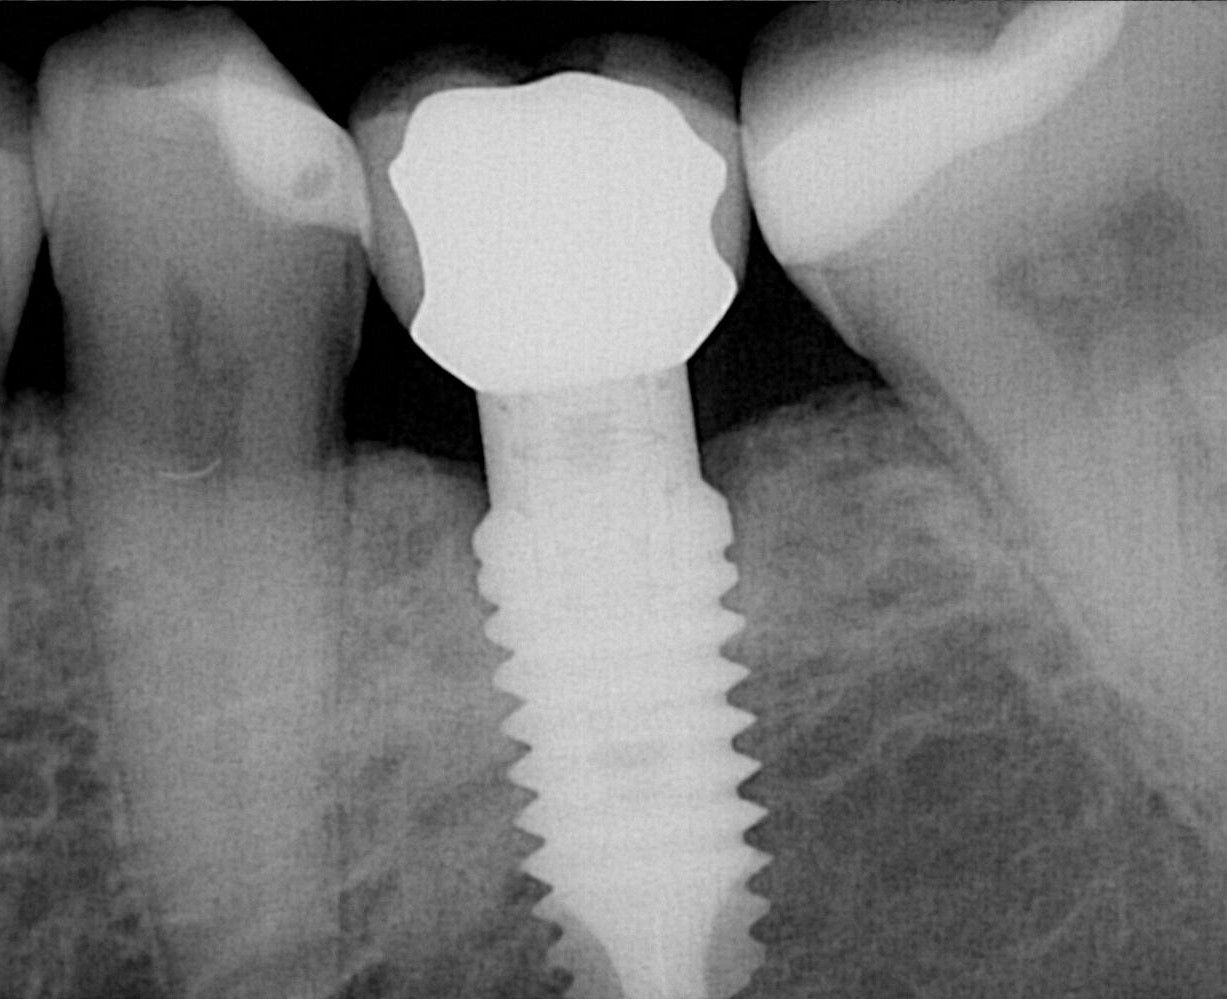

Son elementos con forma de tornillo elaborado con titanio, un material biocompatible, que no provocan rechazo y se integran de forma natural en el hueso del maxilar o la mandíbula.